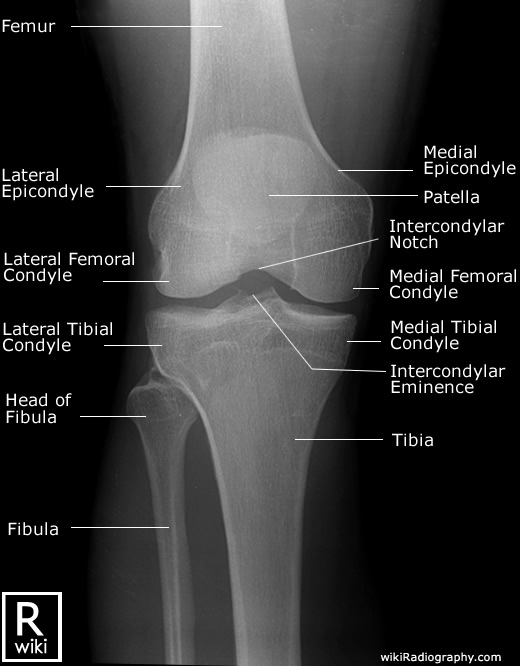

Spine Radiographic Anatomy

| AP view (Cervical) | AP view (Thoracic) |

![]() |

| AP view (Lumbar) | AP view (Sacrum) |

1) http://www.wikiradiography.net